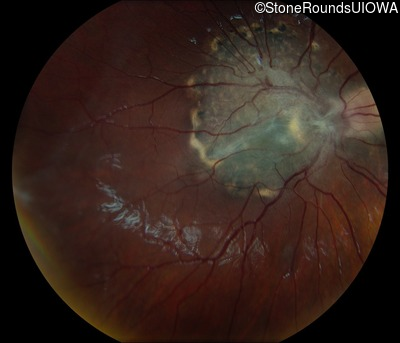

This 9 year old male was noted to have some crossing of his eyes at 2 months of age and the eye exam which followed identified a retinal lesion in the right eye. When he was six years old an epiretinal membrane was noted in his left eye. Two years later it was decided that it was a thin hamartoma in that eye as well. He underwent neuroimaging at age 7 which identified bilateral acoustic neuromas.